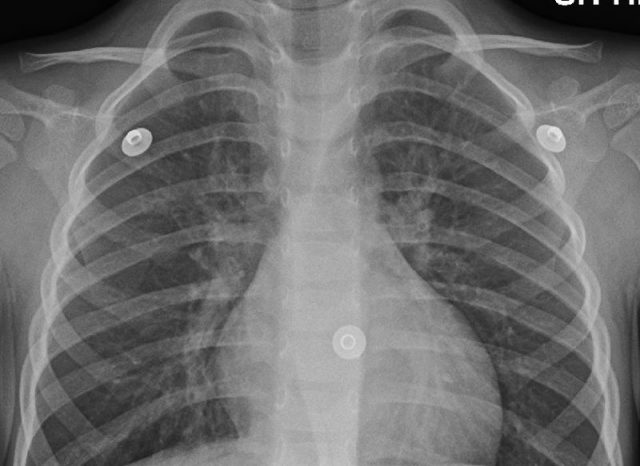

Akutní zánět průdušek neboli bronchitida se projevuje zpočátku suchým dráždivým, později vlhkým kašlem, bolestí za hrudní kostí a vykašláváním žlutých nebo zelených hlenů. Přidružit se může také horečka, bolest hlavy či krku, dušnost a únava.

Ohrožující je onemocnění zejména pro lidi trpící srdeční chorobou, onemocněním plic či astmatem. Nemoc se léčí zejména symptomaticky, v případě bakteriální infekce předepíše lékař antibiotika.